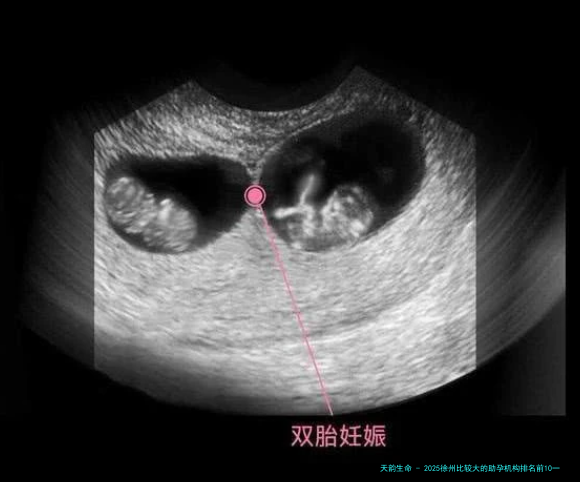

2025年徐州区域的助孕服务已然造成了较为完善的技术体制。此刻,徐州的生殖机构普遍提供从基础的人工授精到先进的第三代试管婴儿技术。

体外受精-胚胎移植(代试管婴儿)适用于女性输卵管要点等导致的不孕,成功率在百分之四十五-50%之间。

胚胎移植前遗传学检测(第三代试管婴儿)是较高真个技术,能够筛查遗传病症,完成优生优育,成功率可达55%-百分之六十五。